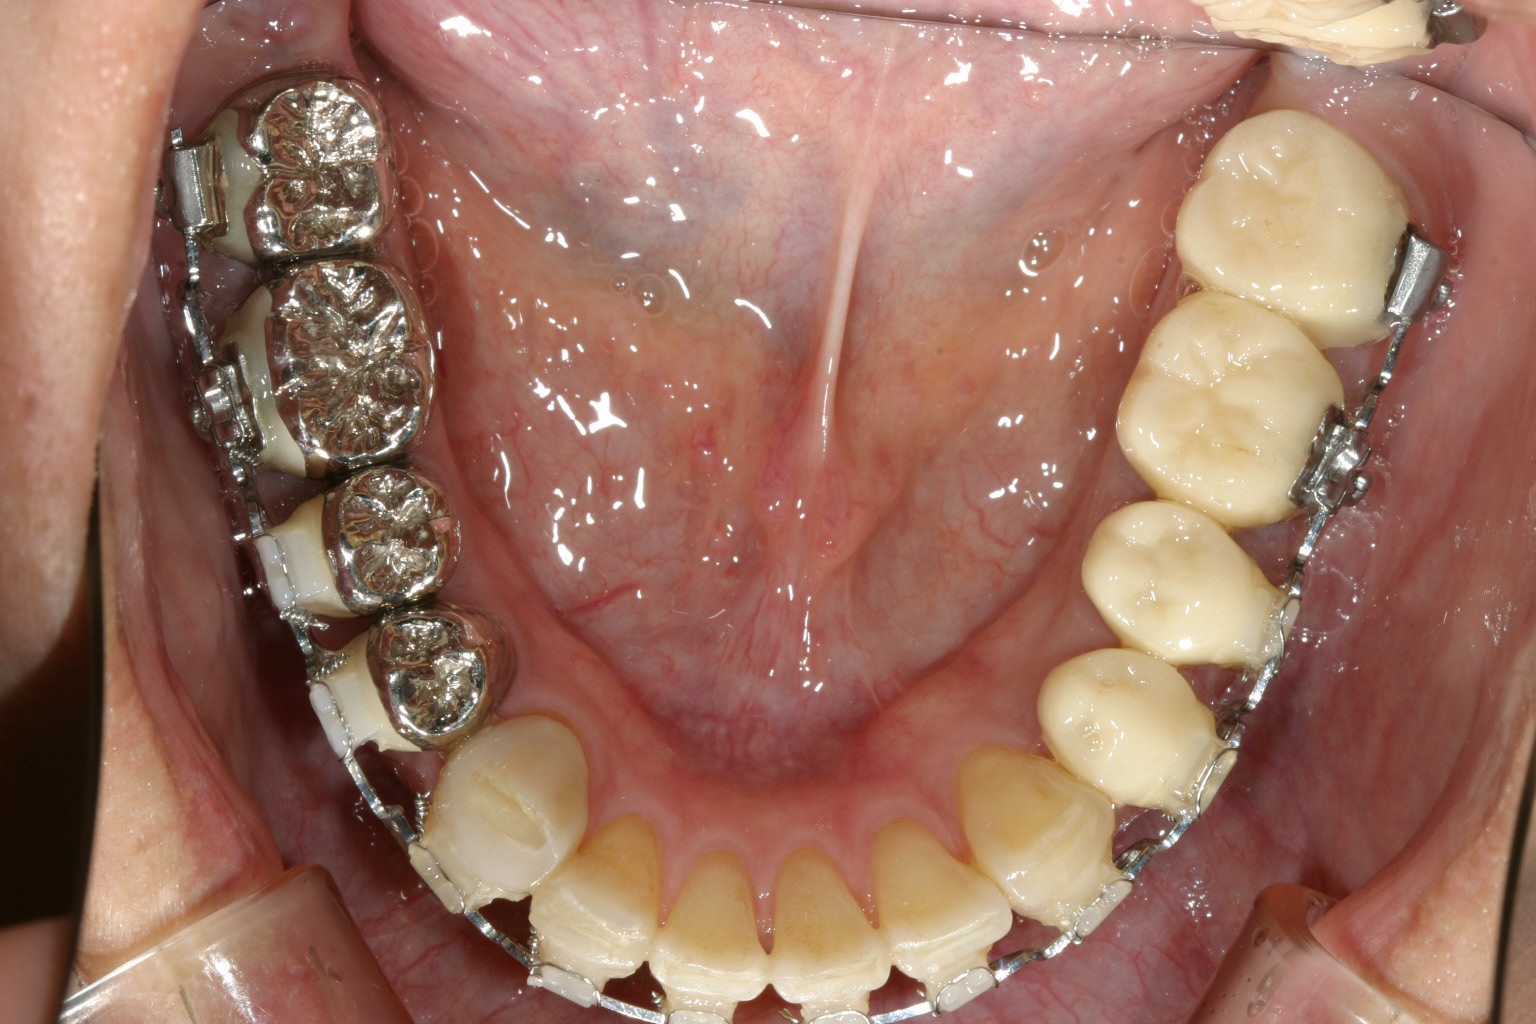

下顎は8本の臼歯を仮歯に変更して顎位を修正したのちマルチループワイヤーにてかみ合わせの調整を行う。 最初右にも左と同様のプラスティックレジン冠を入れるが顎位が右に戻る傾向があり咬耗激しく現在の様な金属冠に変更する。(全体的に少し高さを挙げて特に右側を沢山挙げる事により顎位が左へシフトさせる) アーチフォームもU字変更している。

下顎も矯正による咬合修正も終わり左右臼歯にジルコニア冠で8本補綴完了する